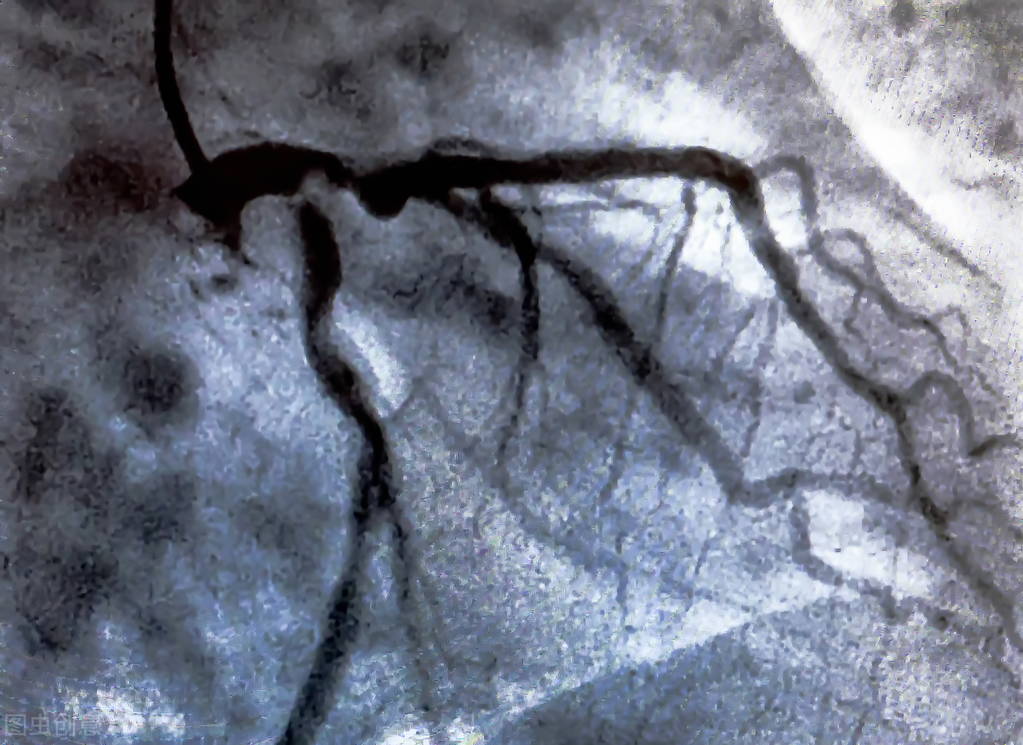

第二天老许就被推进了导管手术室,手上做了动脉穿刺,做了冠状动脉造影,这一造影全明白了。他的三支冠状动脉堵塞的病变比原来没有好一点点,反而严重了许多,原来那两个堵塞50~60%的血管,现在已经堵塞80~90%了,原来堵塞30%的血管,现在已经堵塞50%了。这结果很出乎老许的意料,但是在医生看来这是意料之中的事情,当时就有堵塞了,医生建议他规范吃药,或许能控制,到现在这样子就有点麻烦了。